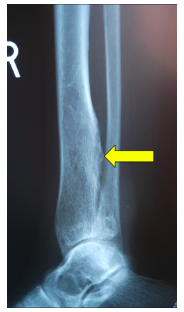

Radiographic imaging is used to help form a diagnosis of secondary chondrosarcoma. These include X-Ray, MRI, CT and Bone Scans

An example of an X-Ray is shown.